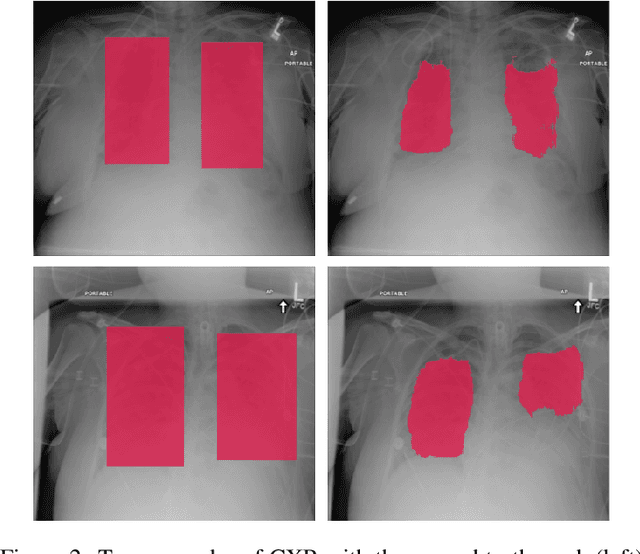

Abstract:Deep learning semantic segmentation algorithms can localise abnormalities or opacities from chest radiographs. However, the task of collecting and annotating training data is expensive and requires expertise which remains a bottleneck for algorithm performance. We investigate the effect of image augmentations on reducing the requirement of labelled data in the semantic segmentation of chest X-rays for pneumonia detection. We train fully convolutional network models on subsets of different sizes from the total training data. We apply a different image augmentation while training each model and compare it to the baseline trained on the entire dataset without augmentations. We find that rotate and mixup are the best augmentations amongst rotate, mixup, translate, gamma and horizontal flip, wherein they reduce the labelled data requirement by 70% while performing comparably to the baseline in terms of AUC and mean IoU in our experiments.